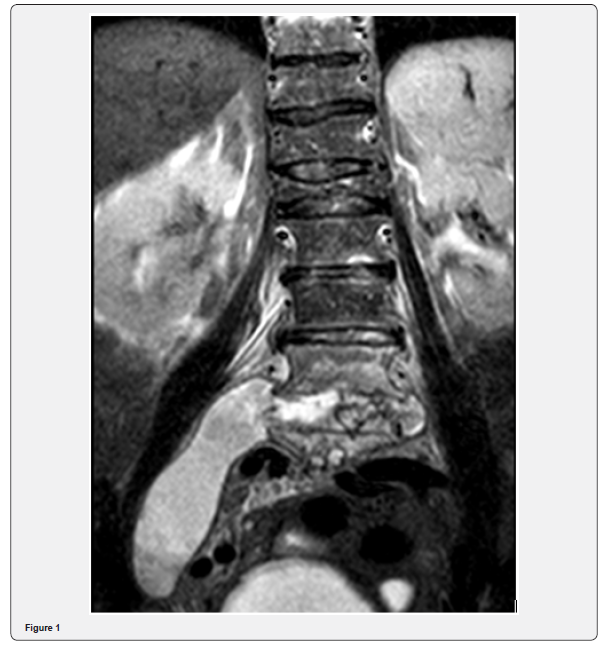

A 79-year-old patient with a history of osteoarticular disease and cerebrovascular disease was admitted to our Service for the studyfever of unknown origin. She complained of fever, low grade, with a few weeks of evolution, but without associated low back pain, hypersudoresis, weight loss, asthenia or anorexia. Initial physical examination was unremarkable. Laboratory results showed inflammation, but extensive testing for bacteriological and viral serology was negative. Throughout the hospitalization the patient only occasionally referred to low back pain, related to said antecedent of compressive fracture ofL1 and labeled L5-S1 listesis and she only had one peak of low grade fever (37,3 ºC). In what concerns of the rest of the study, CT scan of the throrax, abdomen and pelvis without alterations, colonoscopy and high endoscopy unremarkable. She was discharged to mantaining study in external consult and returned 3 weeks later with complaints with low back pain and persisting low grade fever. A CT scan of the column was request, and showed extensive process of spondylodiscitis with vertebral abscess. An abscess puncture was performed and microbiology cultures send to the laboratory. Magnetic ressonance of the column was also performed and described an extensive infectious process, with starting point in spondylodiscitis, involving the bodies L3, L4 and L5 vertebrae. The infectious process has intracanal expression, with an emphasis on anterior epidural predominance and collection from L3 to L5-S1, which involves the corresponding nerve roots in its path and in the lateral recesses. There is a marked prior list of L5 on S1 grade II of Meyerding due to degenerative changes. The corresponding conjugation holes are not large. Change of sign of parts vertebral, suggestive of osteomyelitis from L3 to L5, with components abcedados associated with pre-vertebral, with a maximum thickness of 7.2mm, to the left, and massive collection abcedada with path along the muscle psoas, with 12cm of extension, to the right (Figure 1). Microbiology of pus identified the presence of mycobacterium tuberculosis and the patient initiated targeted therapy with isoniazid, rifampicin, pyrazinamide and ethambutol.